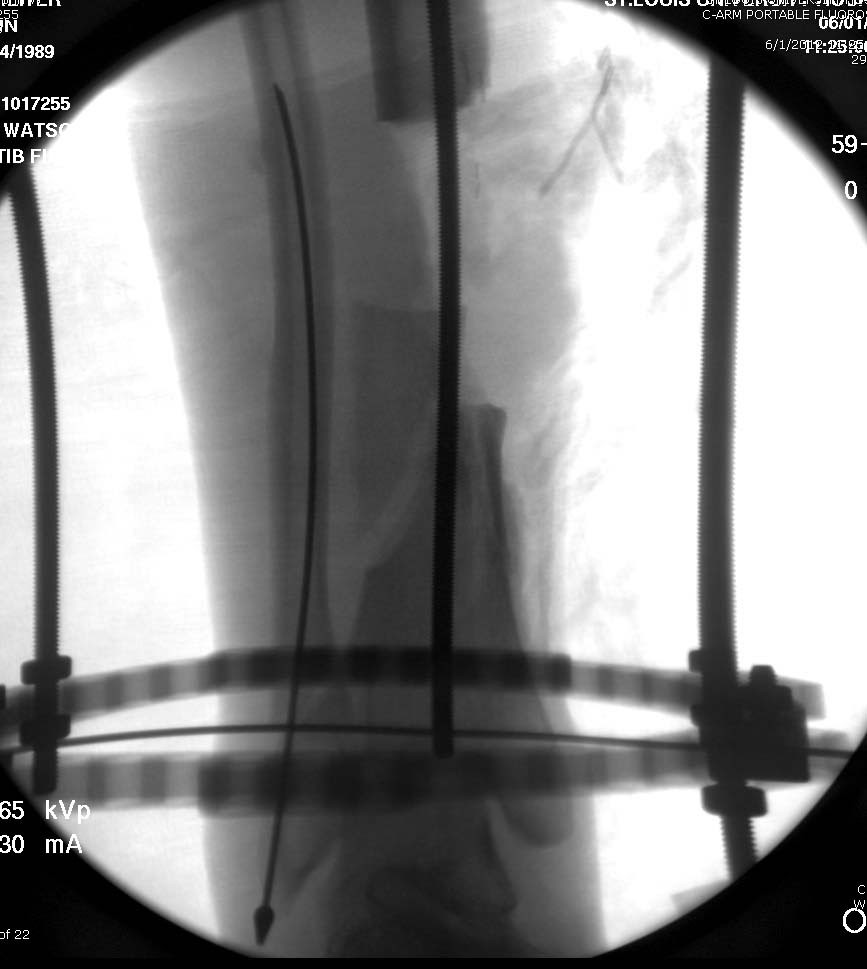

Данный случай не огнестрельная рана, а результат мотоциклетной аварии.

Независимо от повреждения при таких обширных дефектах мягких и костной

тканей применяется схожая тактика. Как видно, после нескольких I&D для

создания “pseudo membrane” применили цилиндрический блок из цемента.

Дефект мягких тканей закрыли свободным Anterior Thigh Graft. Из малого

доступа цилиндр удален небольшими кусочками, а пространство заполнили

бусами для освобождения пространства. По мере приближения регенерата

освободили пространство удалением бус через небольшой разрез. Этап

созревание регенерата можно было ускорить усилением интрамедуллярным

гвоздем, но решили закончить методом Илизарова.